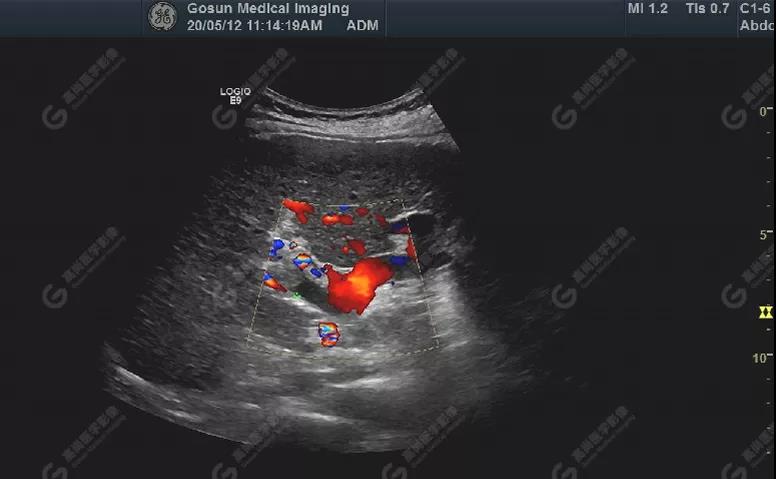

門靜脈右支內(nèi)低回聲處可見(jiàn)血流充盈缺損,其內(nèi)部無(wú)明顯血流

超聲所見(jiàn)肝包膜不光滑,實(shí)質(zhì)回聲增粗,不均勻,以右葉顯著,肝內(nèi)可見(jiàn)散在高回聲結(jié)節(jié),最大約7mm×5mm,邊界清,形態(tài)規(guī)則,CDFI顯示高回聲結(jié)節(jié)未見(jiàn)明顯異常血流信號(hào)。門靜脈主干內(nèi)徑約14mm,門靜脈右支管腔內(nèi)見(jiàn)實(shí)性低回聲,大小約23mm×14mm,邊界不清,形態(tài)不規(guī)則,局部與肝組織分界不清,CDFI:門靜脈主干血流緩慢,左支血流充盈好,右支血流充盈缺損,低回聲內(nèi)未見(jiàn)明顯血流信號(hào)。超聲造影:經(jīng)左側(cè)肘靜脈團(tuán)注超聲造影劑sonovue2.0ml。肝組織開始增強(qiáng)時(shí)間8秒,病灶開始增強(qiáng)時(shí)間11秒,邊界清晰。脈期呈均勻高增強(qiáng),至門脈期和延遲期消退為低增強(qiáng)。延遲期肝S7段局部回聲減低,范圍約82mm×50mm,內(nèi)見(jiàn)一低增強(qiáng)區(qū),范圍約13mm×16mm。